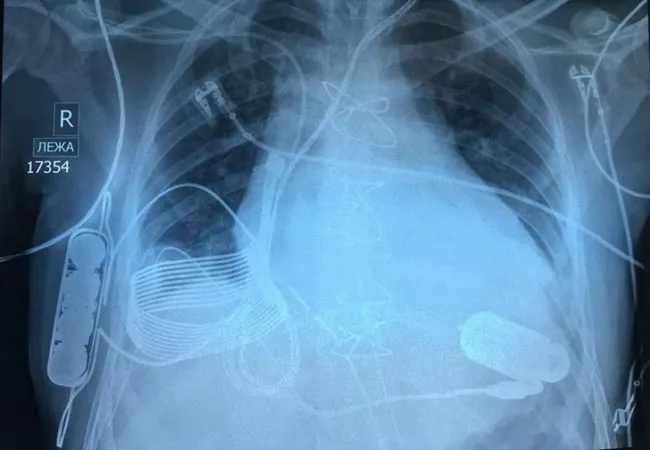

11 การเอ็กซ์เรย์หน้าอกของคนที่มีหัวใจเทียม (bionic heart) ที่กำลังชาร์ตแบบไร้สาย